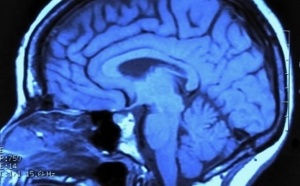

Un pas de plus vers la télépathie 10/09/2014Insolite 10/09/2014Un championnat du monde de labour 09/09/2014Insolite 09/09/2014Insolite 08/09/2014Insolite 06/09/2014Insolite 05/09/2014 |